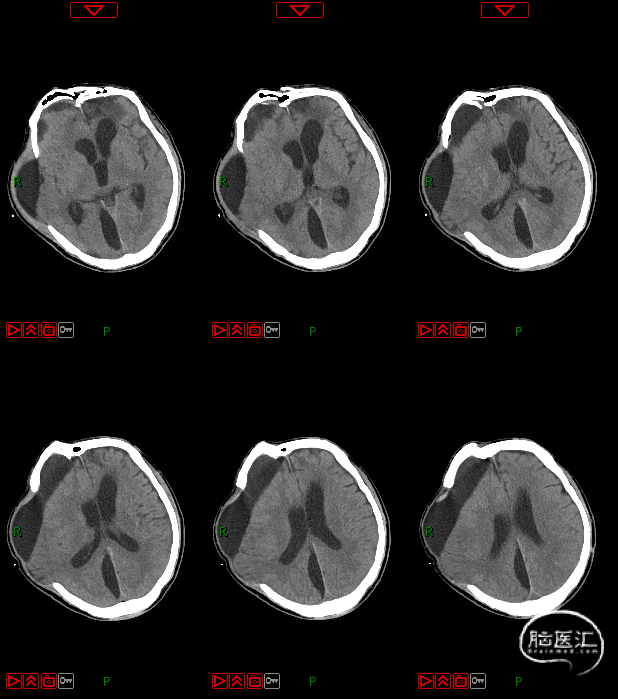

4. 动态复查头部CT

8月21日复查CT:硬膜下积液增加,脑室扩张明显,间质性水肿加重;对患者治疗方案进行调整,转神经外科治疗。

脑积水的处置

第五阶段(颅骨修补术)

7月16日行PEEK材料颅骨缺损修补术。